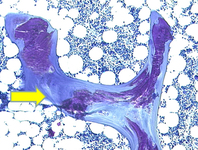

Fotomicrografia de biópsia óssea transilíaca normal demonstrando osteoide mineralizado (mostrado em roxo)

Do acervo de Bridget Sinnott, MD; usado com permissão